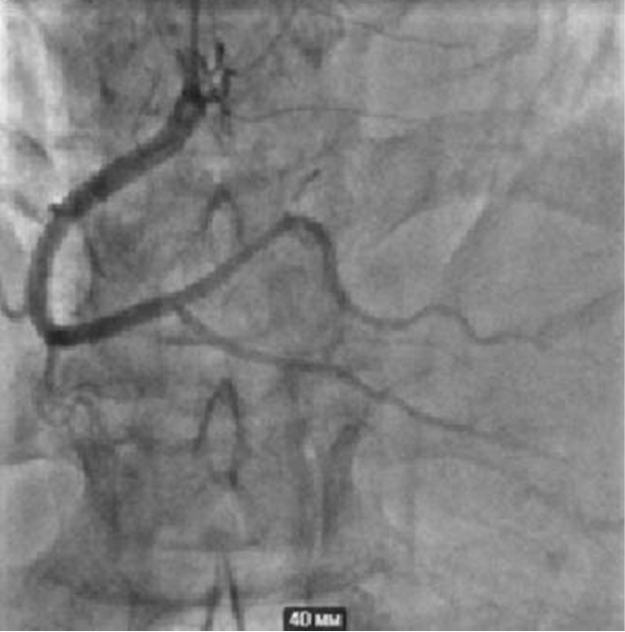

Taking into account his dyspnea on exertion and reduced exercise tolerance, the patient underwent coronary angiography, which revealed 75% proximal stenosis of the diagonal branch (D1) of his left anterior descending artery (LAD). His left circumflex coronary artery and right coronary artery didn’t have any significant stenosis (see Fig. 3 and 4). Conservative treatment was recommended in absence of indications for percutaneous coronary intervention (SYNTAX Score — 2 points).

Fig. 4. Left anterior descending artery and circumflex artery without significant stenosis